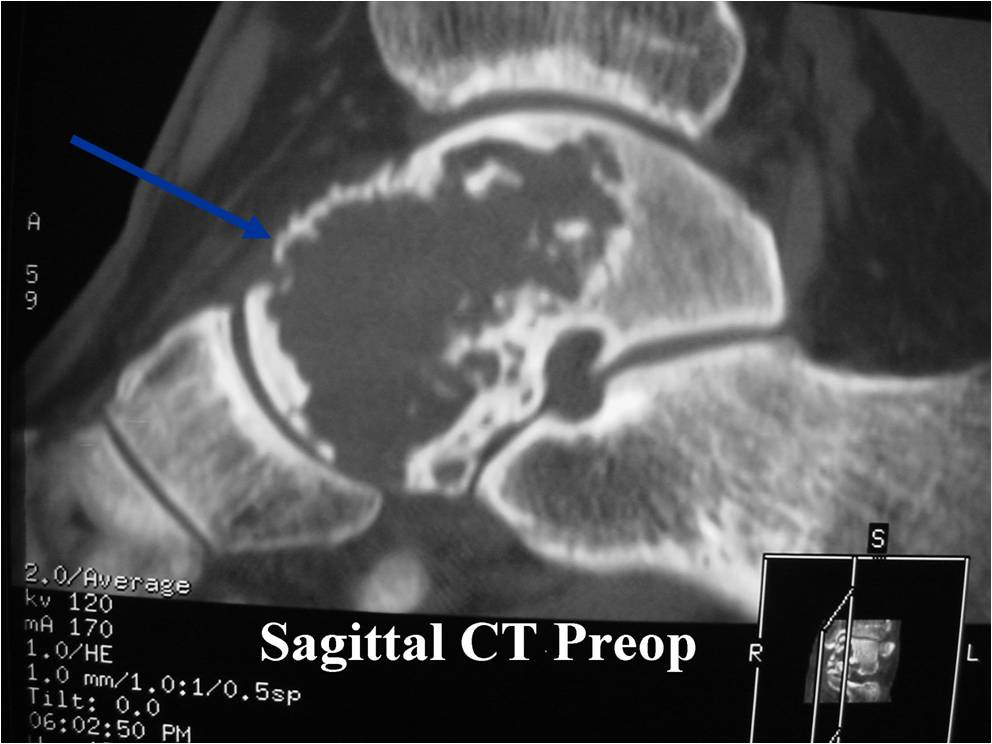

Radiographic Presentation

- Presents as a highly defined/well circumscribed geographic oval/round lytic defect

- Surrounded by rim of sclerotic bone

- Usually in epiphyseal region

- Lesion ranges from 3 cm to 6 cm diameter

- Usually radiolucent

- May have fine trabeculae and irregular calcifications

- Calcifications are often better detected with a CT scan but are not uniformly present

- Lesions may expand the bone and new periosteal bone may form

- Bony end plate, cortex, bone contour are unaffected

- (CT appearance)

- Most useful for detecting subtle mineralization not apparent on X-rays

- Useful for identifying intact periosteum around any expansile soft tissue component

- surrounding thin reactive shell of bone/mineralization (Egg Shell Rim of Calcification)

- helps place the tumor in a benign category

- helps evaluate:

- bony quality

- extent of bone and cortical destruction

- whether the subchondral plate of bone adjacent to the articular cartilage has been destroyed or is intact